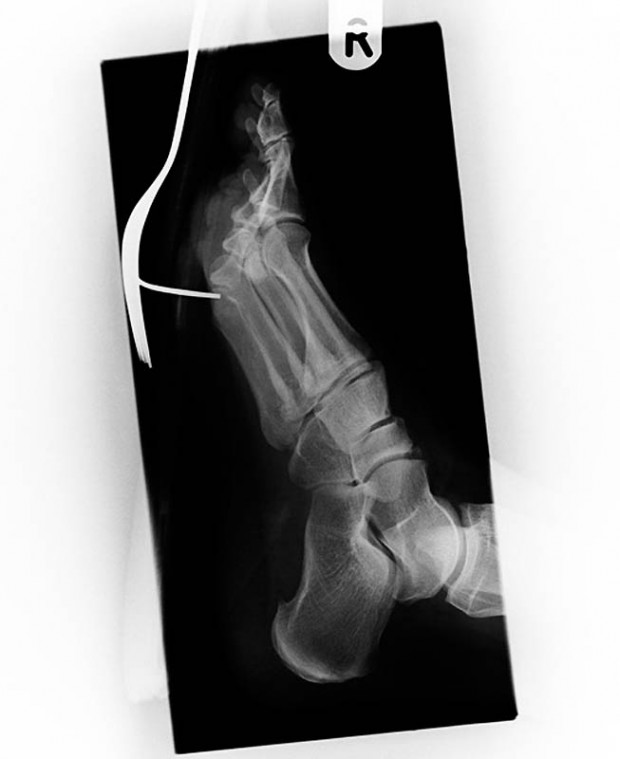

3. Старинный рентгеновский снимок ступни солдата англо-бурской войны (1899-1902) с огнестрельным ранением. Пуля застряла в плюсневой кости между большим и вторым пальцами.